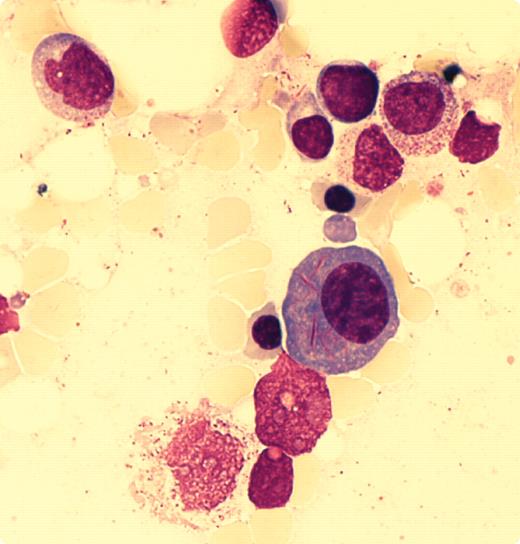

An 83-year-old woman with chronic gastrointestinal problems developed retinal vein thrombosis. Laboratory tests revealed an erythrocyte sedimentation rate of 45, renal dysfunction (GFR 25 mL/min), and mild anemia (hemoglobin 10 G/dL) with normal white cells and platelets. β2-microglobulin was elevated at 8.06 mg/L. A plasma cell dyscrasia was suspected and immunoglobulin testing showed monoclonal IgG, κ in the serum (28.9 g/L) with free κ chains (1.2 g/L), and κ light chains in the urine (10.2 g/L). Bone marrow aspirate contained ∼ 10% plasma cells (CD38+CD138+) with long, slender, Auer-like inclusions (see figure) in 50% of the cells. Approximately 14% of the plasma cells had multinuclear forms.

Auer-like inclusions raise the possibility of acute nonlymphocytic leukemia (ANNL). However, the patient has been followed since the previous year with no evidence of ANNL. Rare instances of Auer-like inclusions within plasma cells have been previously reported. The mechanism by which they occur and their pathophysiologic significance are not understood. Continued observations on this patient may provide more information on the unusual occurrence of Auer rods in a patient with monoclonal gammopathy.